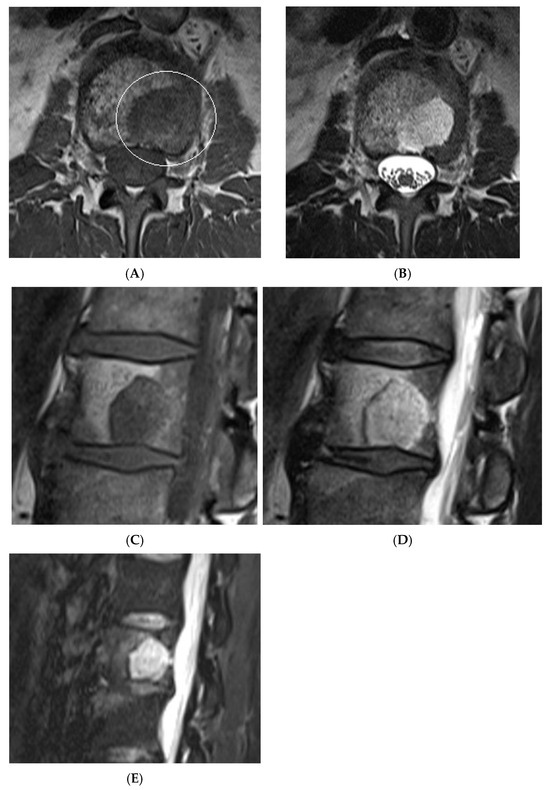

Figure 10.

Typical haemangioma of the vertebral body. (A) T1W axial MRI. (B) T1W sagittal MRI. (C) T2W sagittal MRI. (D) STIR sagittal MRI.

Figure 11.

Atypical haemangioma at sacrum. (A) Axial CT. (B) T1W axial MRI. (C) Axial STIR MRI. (D) Sagittal STIR MRI.

Figure 12.

Aggressive spine haemangioma with involvement of the vertebral body and posterior elements with cortical expansion. (A) Axial T1W MRI. (B) Axial T1W post-contrast MRI. (C) Axial STIR MRI. (D) Sagittal T1W MRI. (E) Sagittal STIR MRI.

Figure 13.

Aggressive spine haemangioma. (A) Axial CT showing lytic lesion within the left-side posterior aspects of the vertebral body with cortical destruction. (B) Axial T2W MRI with the expansile lesion encroaching within the spinal canal and neural foramen. (C) Sagittal T1W MRI. (D) Sagittal T2W MRI and (E) sagittal STIR MRI, demonstrating a more vascular component of the lesion along with expansile component effacing the neural foramen.

Some fat-containing lesions present atypically, as described above in the example of atypical and aggressive haemangiomas. Despite their appearance, the key differentiating feature between different types of intraosseous haemangiomas is their histologically; vertebral haemangiomas are considered hamartomatous lesions, composed of variable proportions of vascular channels within a fatty stroma [14,15]. Their appearance on MRI is thus largely determined by the ratio of these two components [15]. Typical haemangiomas are characterised by a predominance of fatty stroma, resulting in high signal intensity on T1-weighted images and signal suppression on fat-saturated sequences. In contrast, atypical haemangiomas exhibit a higher proportion of vascular channels, often accompanied by interstitial oedema and reduced fat content. These features contribute to their more heterogeneous isointense or even low signal appearance on T1-weighted imaging [16], which can mimic more aggressive or malignant pathology (Figure 10, Figure 11, Figure 12 and Figure 13). Intralesional fat content assessment and quantification can therefore assist with diagnosis and management decision-making in terms of imaging follow-up versus histological diagnosis (biopsy).